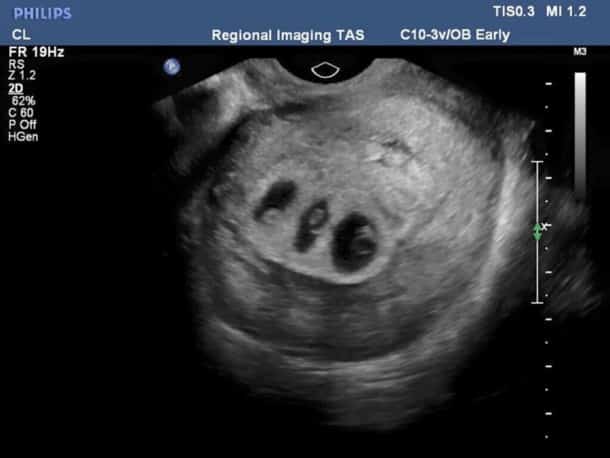

C’est lors d’une échographie que le couple découvre la cause de ce ventre si rond et si gros. En réalité la maman n’attend pas un mais trois bébés ! Or, l’un des bébés est bien une petite fille mais n’est pas assez oxygénée dans le ventre. Elle risque de mourir et tout va devoir être mis en œuvre pour la sauver.